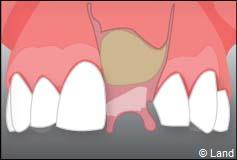

Le chirurgien-dentiste après une anesthésie locale pratique une incision, puis il décolle la gencive pour accéder à l’os alvéolaire.

L’implant est placé dans l’os le plus souvent par vissage et doit avoir une liaison forte avec l’os. Le praticien replace alors la gencive et pose des points de suture.

Exemple d’un implant unitaire pour remplacer une dent antérieure manquante.